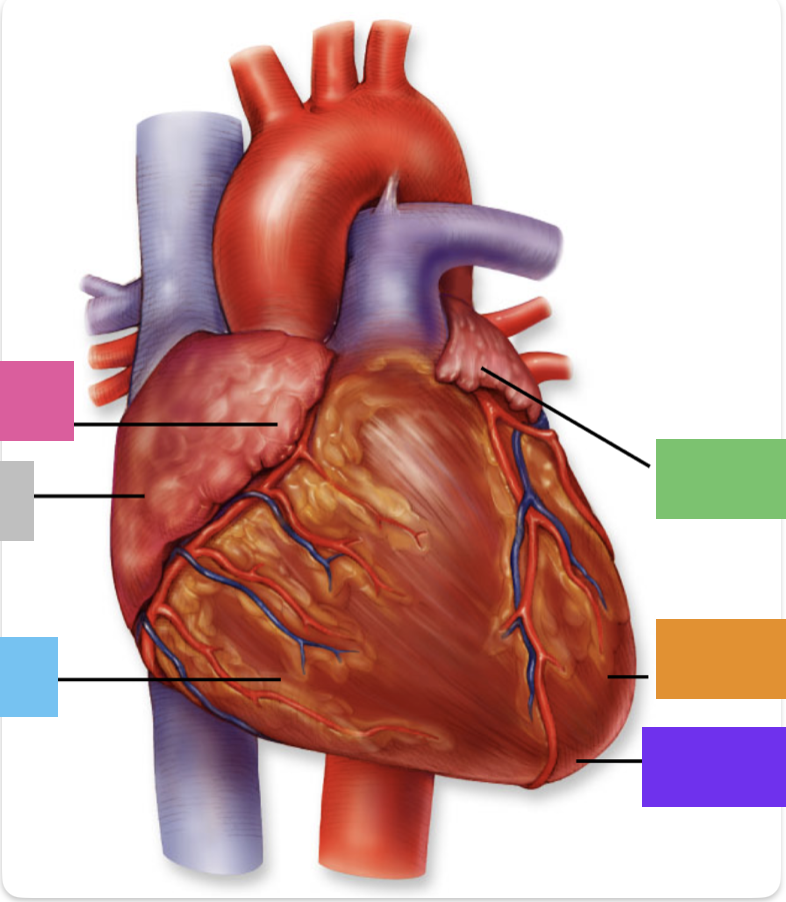

light purple

base

purple

apex

grey

right atrium

pink

right auricle

green

left atrium

green

left auricle

blue

right ventricle

orange

left ventricle

green

coronary (atrioventricular) sulcus

pink

interatrial septum

dark blue

interventricular septum

green

anterior interventricular sulcus

green

posterior interventricular sulcus

right coronary artery

posterior interventricular artery

left coronary artery

anterior interventricular artery

circumflex artery